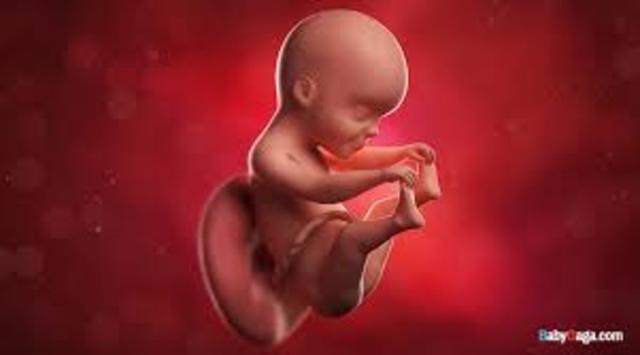

• during the end of the fetus period

during the end of the fetus period

week 9 to birth, the fetus continuous to grow, legs,head,fingers etc. At 10 weeks it starts to swallow and kick. Week 11 its almost fully formed. Week 12 baby starts to open and close its fingers. Mouth will start sucking movements. Intestine will move into abdomen cavity. Week 13 first trimester ends finger prints star to form. It is almost 3 inches long.